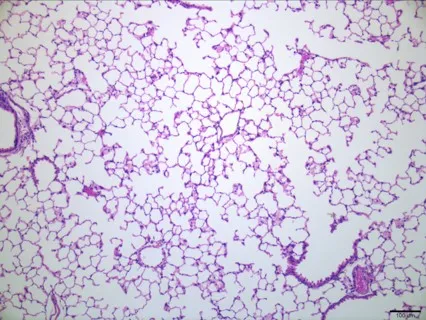

Their latest study, published in Molecular Therapy, shows that the approach can improve lung function and structure in a mouse model of surfactant protein C (SP-C) deficiency. This is a particularly challenging form of the disorder, as it involves the production of a toxic form of SP-C in addition to the loss of the normal form of SP-C.

To address this challenge, the team designed a dual-purpose gene therapy that uses an adeno associated virus (AAV) to produce the effective form of SP-C while also silencing the toxic form.